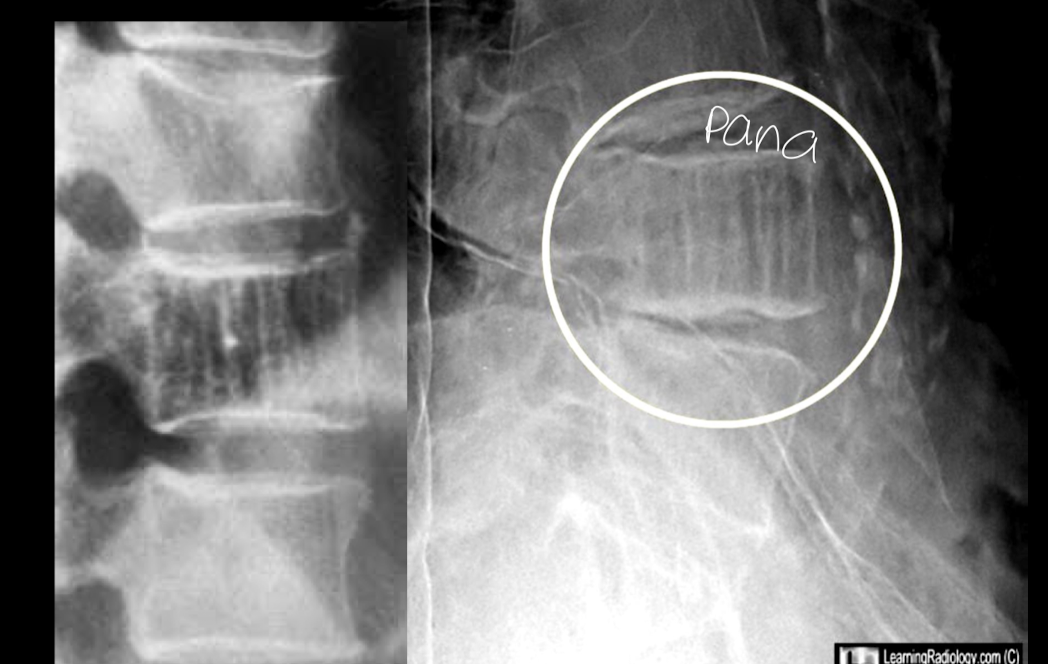

RX

A

signo de la tela de pana

signo de la empalizada o barrotes